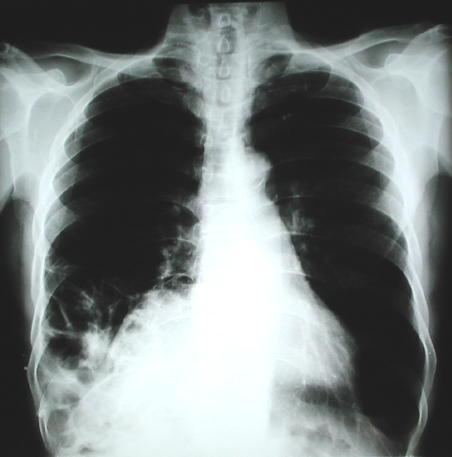

• Una radiografía torácica anormal, en octubre del 1999, reportada inicialmente como reacción pleural de tipo residual, en evaluación traumatológica por disfunción de la articulación del tobillo izquierdo sugiere evaluación neumonológica, los nuevos estudios radiológicos del tórax demuestran patología caracterizada radiopacidad basal derecha con borramiento del hemi diafragma e imágenes de aspecto hidroaereo que plantea la posibilidad de una hernia diafragmática de contenido gastrointestinal de probable etiología pos traumática.

• Radiología del Tórax

Radiología Posteroanterior del tórax

Radiología del tórax: